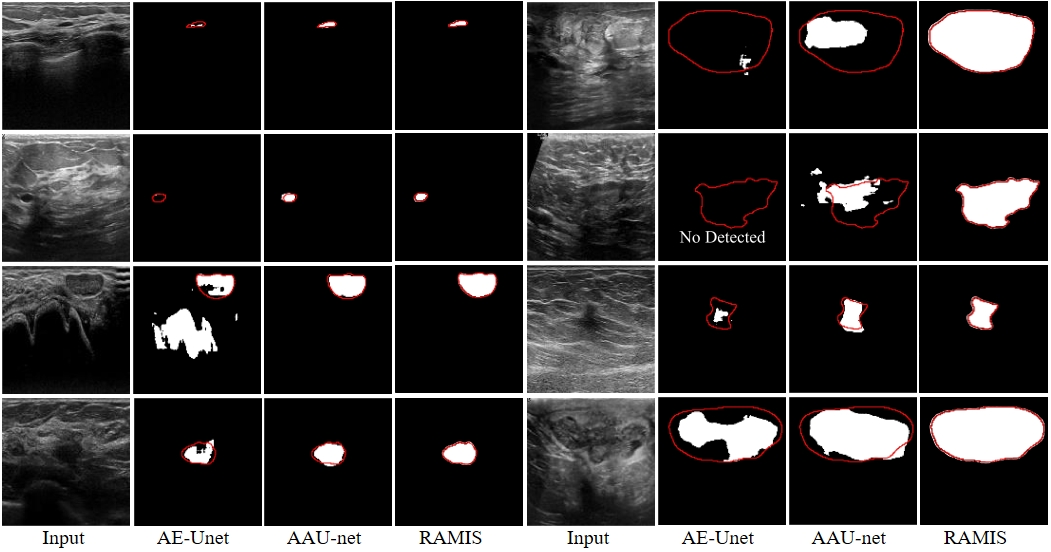

Fig. 8-1 Qualitative comparison results between RAMIS and AE-Unet [3], AAU-net [4] on the BUSI dataset. The red outline represents Ground Truth. The prediction results of AE-Unet [3] and AAU-net [4] are derived from the report of AAU-net [4].